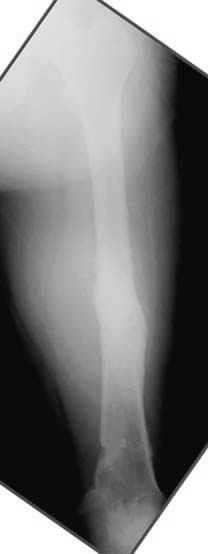

Несколько снимков из моей коллекции, чтобы разьяснить, почему мы до сих пор делаем различные варианты остеотомии.

На рисунке N1 предоперационный план лечения ложного сустава шейки бедра- линия ложного сустава, угол и направление введения импланта, клиновидная остеотомия в градусах и миллиметрах, второй снимок после коррекции, расчет, на сколько удлиняется конечность и размеры импланта;

N3 рисунок окончательный снимок, после операции моя рентгенограмма должен выглядеть примерно как эта картина. На N4 снимке клин перед удалением; N5 послеоперации 3 нед.; N6 окончательная рентгенограмма.

Отправитель: Evgueny Tschekashkin 24 Ноябрь 2004, 21:09

хотя даже если бы и инфекция , то nail exchange с рассверливанием канала - вариант дебрайдмента) Я думаю, что последовательность развития событий:

Узкий к-м канал - тонкий гвоздь- усталостный перелом дистальных винтов - развитие нестабильности и как ее результат остеолиз вокруг гвоздя - деформация анатомической оси бедра. Похоже, что я понял почему аппарат, а не новый гвоздь:-)